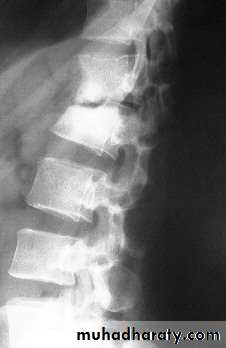

In the spine (Pott’s disease), the most common site is the thoracolumbar spine, it is usually involve the anterior part of the vertebral body adjacent to the intervertebral disc space which is also involved early in the disease.

Abscess tracks downward along the vertebral column or it may extend toward the spinal canal.

In the spine, pain may be slight. Consequently the patient may not present until there is a visible abscess (usually in the groin or the lumbar region to one side of the midline) or until collapse causes a localized angular kyphosis (gibbus).

In the spine the characteristic appearance is one of bone erosion and collapse around a diminished intervertebral disc space (kissing vertebrae). The soft-tissue shadows may define a paravertebral abscess.